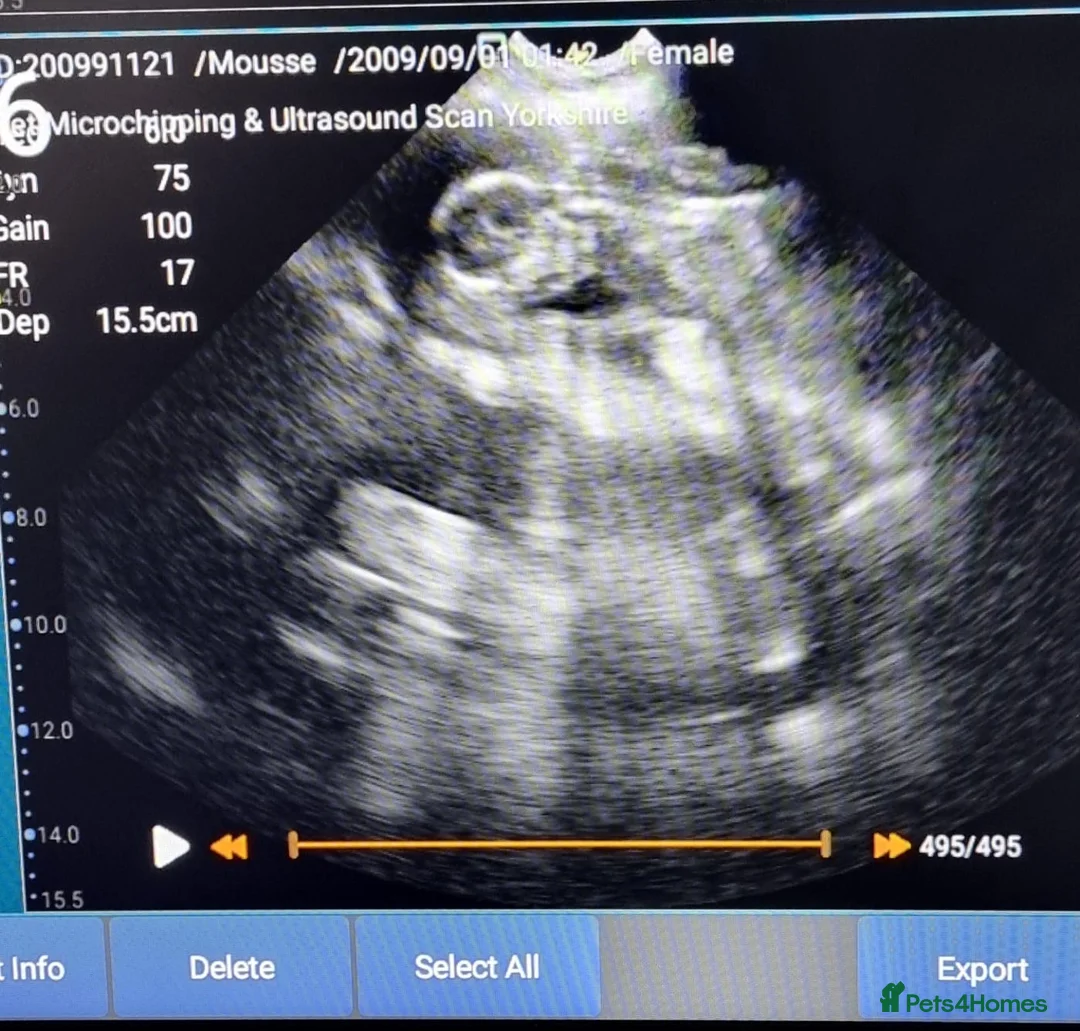

Today we have been scanned and confirmed 6+ puppies, we are currently around 6 weeks so puppies should be here in around 3 weeks time. Mum & Dad are both pedigreed Bernard’s that have both been health tested before this mating. Mum has previously had a litter of 11 with the same stud last year, please see pictures of litter in the photo gallery. Puppies will be brought up in our family home with 4 other family dogs so they will be well socialised by the time they leave. Puppies will all be health checked, vaccinated, wormed and flea treated on leaving. Puppies will be weaned onto raw as that is what we feed mum and she thrives on this, each puppy will leave with their own individual puppy pack including some of the raw they will be on, toys and other little bits.